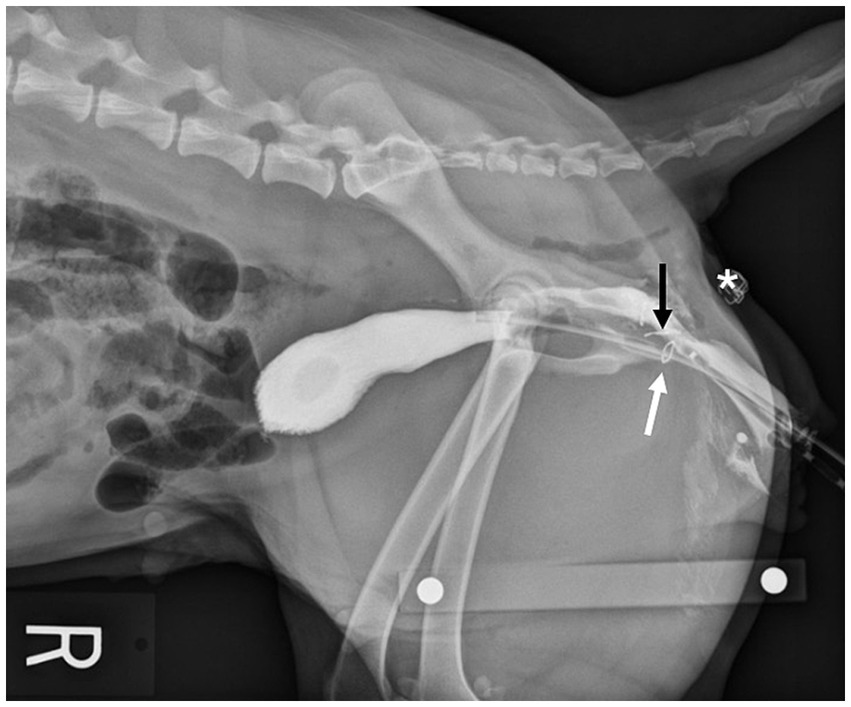

Immediately postoperatively, cadavers of both groups had right lateral pelvic radiographs taken with a calibration marker in the field. The distance between the location of the anastomosis (Group A) or vaginectomy site (Group B) and the skin incision was measured. In Group A, positive contrast cystourethrography was performed to give detail regarding location of the bladder and urethra in comparison to the vaginal anastomosis site (Figure 4). To perform the cystourethrogram, iodinated contrast was injected into the bladder (Omnipaque, iohexol 240 mgI/mL), and a right lateral radiograph was taken.

Figure 4

www.frontiersin.org

Figure 4. Lateral radiograph of a Group A cadaver. Staples placed at the urethral papilla (white arrow) and vaginal anastomosis site (black arrow) orient the viewer to the location of the urethra in respect to the anastomosis. Location of the transverse skin incision (*).